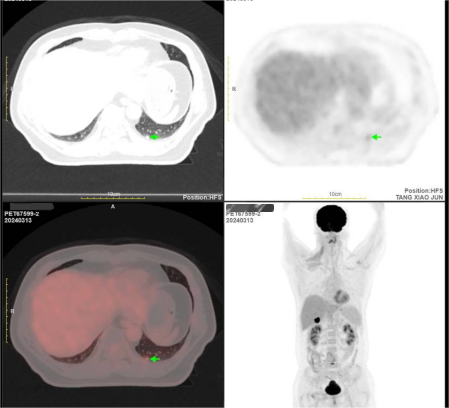

2024-03复查PET/CT:1.右侧腮腺肿物切除术后改变,术区未见肿瘤复发征象。颈部未见肿大淋巴结。与 2023-09-25本院PET-CT所示大致相仿。2.对比前片,原肝S7转移灶消失,局部治疗后改变。肝S6包膜下新增转移灶。3.对比前片,左肺下叶后基底段新增胸膜下小结节灶,拟转移可能性大。4.左上颌窦慢性炎症。余部双肺数枚小结节。5.颈椎及上位胸椎弥漫代谢减低,符合放疗后改变。

图片12.png